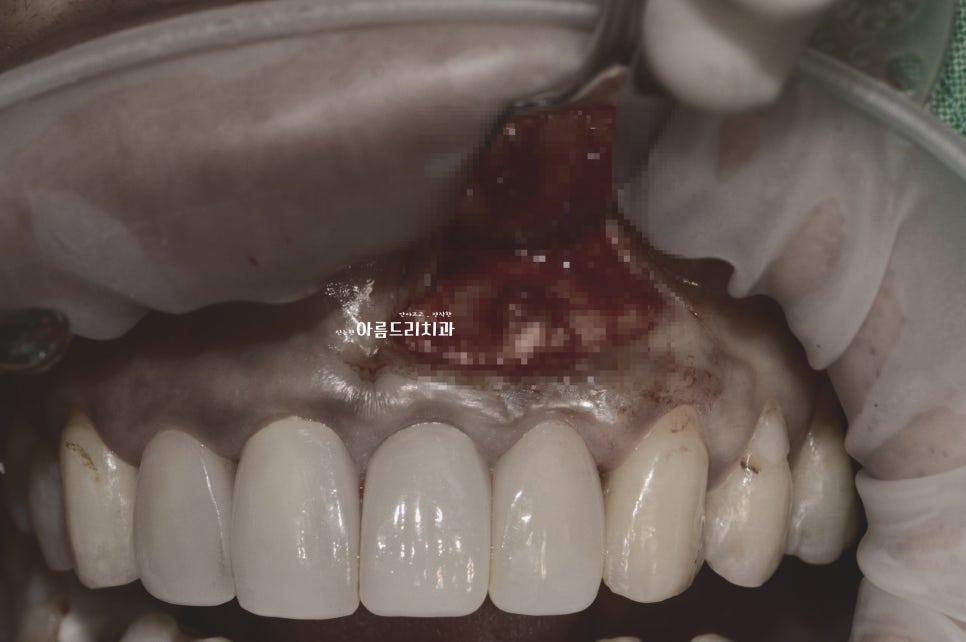

앞니 쪽에 지속적으로 통증이 있어 진단 후 치근단절제술을 시행하기로 하신 케이스로, 뿌리 조직의 염증을 제거 후 부족한 치조골(잇몸뼈)에 뼈이식으로 함께 진행합니다.

치아뿌리염증 _치근단절제술

치근단 절제술 후 뼈이식

*위 시술 사진은 다소 불편한 장면이 포함되어있어 색보정이 되었음을 알려드립니다.